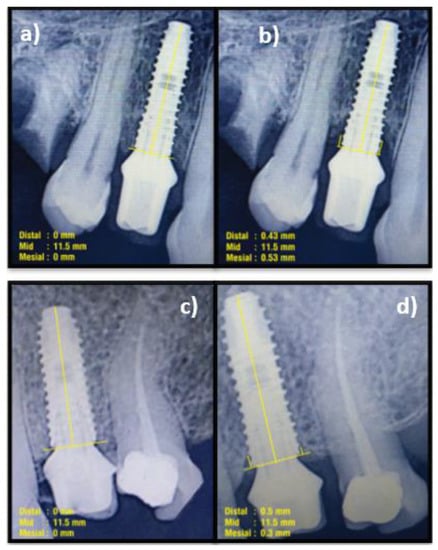

2.8. Follow-Up

Clinical parameters of S-SPS, S-SBS, P-ISD, P-IAL, and PGM were evaluated at six months and 1-year post-functional loading. The MBL and implant survival rate (ISR) were assessed at 1-year post-functional loading (Figure 3a–e and Figure 4a–d).

Figure 4. Measurement of marginal bone loss (MBL). (a) Immediately post-functional loading (Control); (b) 1-year post-functional loading (Control); (c) Immediately post-functional loading (test); (d) 1-year post-functional loading (Test).

Marginal bone loss (MBL) was compared between groups at one-year post-loading. Both the groups showed similar MBL at the mesial and distal aspects at 1-year post-loading, i.e., 0.31 mm in the mesial aspect and 0.28 mm in the distal aspect of the control group; and 0.35 mm in the mesial and 0.33 mm in the distal part of the test group, without any statistical significance (p > 0.05). This indicates that the bone levels had shifted apically with a minimal and comparable amount of MBL in both groups (Table 3).